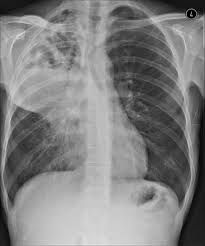

Lung abscess

A lung abscess is a pus-filled cavity in your lung surrounded by inflamed tissue. It usually results from breathing bacteria that normally live in your mouth or throat into the lungs, leading to an infection.